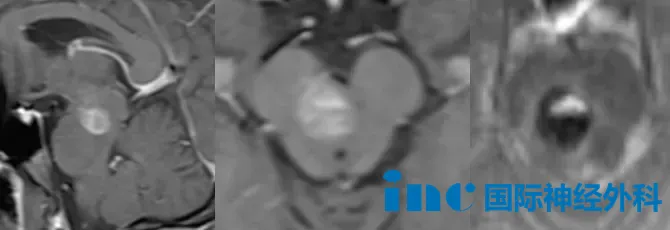

27岁的婷婷,2025年4月因头晕、肢体麻木和复视就医,检查发现脑干海绵状血管瘤,当时选择了保守观察。此后数月,症状一度有所减轻,复查也提示出血在逐渐吸收,但间歇性的麻木感始终没有完全消失。直到2026年2月下旬,症状再度加剧,检查证实发生了二次出血。她辗转咨询了多家医院,得到的答复几乎如出一辙:手术风险极高,面瘫的可能性较大。年轻的她最终做出决定:不再被动等待,选择寻求巴教授主刀的示范手术。

同样罹患脑干海绵状血管瘤的37岁吴先生,在初次出血时出现了面部麻木、讲话含糊、右手无法握笔打字、左腿走路不稳等症状。起初,他也抱着保守观察的态度,希望血肿能够自行吸收。然而病情并没有给他留下等待的余地,短时间内症状持续恶化:无法正常行走,言语愈加混乱,视力也开始模糊。情况危急之下,他将最后的希望寄托于此次巴教授的示范手术。

两位患者,年龄不同,境遇相似——他们都站到了神经外科所谓"手术禁区"的门前。在经历了保守治疗的漫长等待与病情的反复折磨之后,他们做出了同一个选择:将生的希望,交付给巴特朗菲教授那双在手术显微镜下历经四十年磨砺的手。